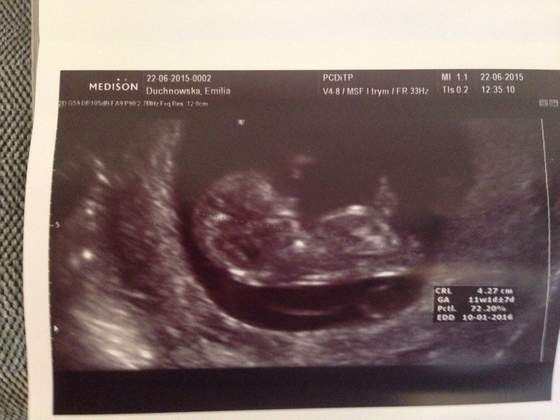

ImageUploadedByForum BabyBoom1434993087.513071.jpg

• ImageUploadedByForum BabyBoom1434993087.513071.jpg

21,7 KB · Wyświetleń: 92